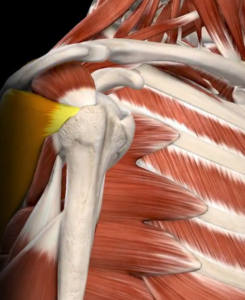

- Infraespinhal – auxilia na rotação externa do ombro.

- Redondo Menor – também participa da rotação externa do ombro.